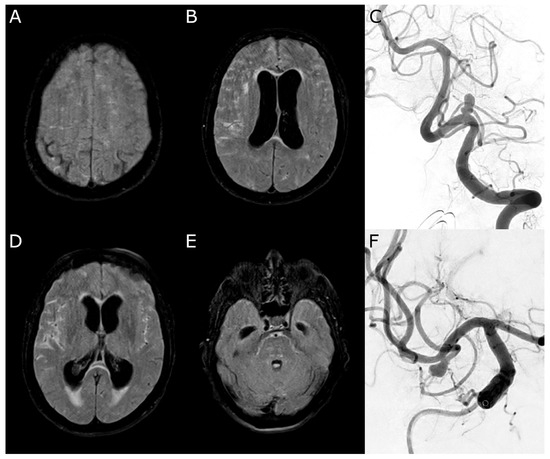

3.11. Case 2